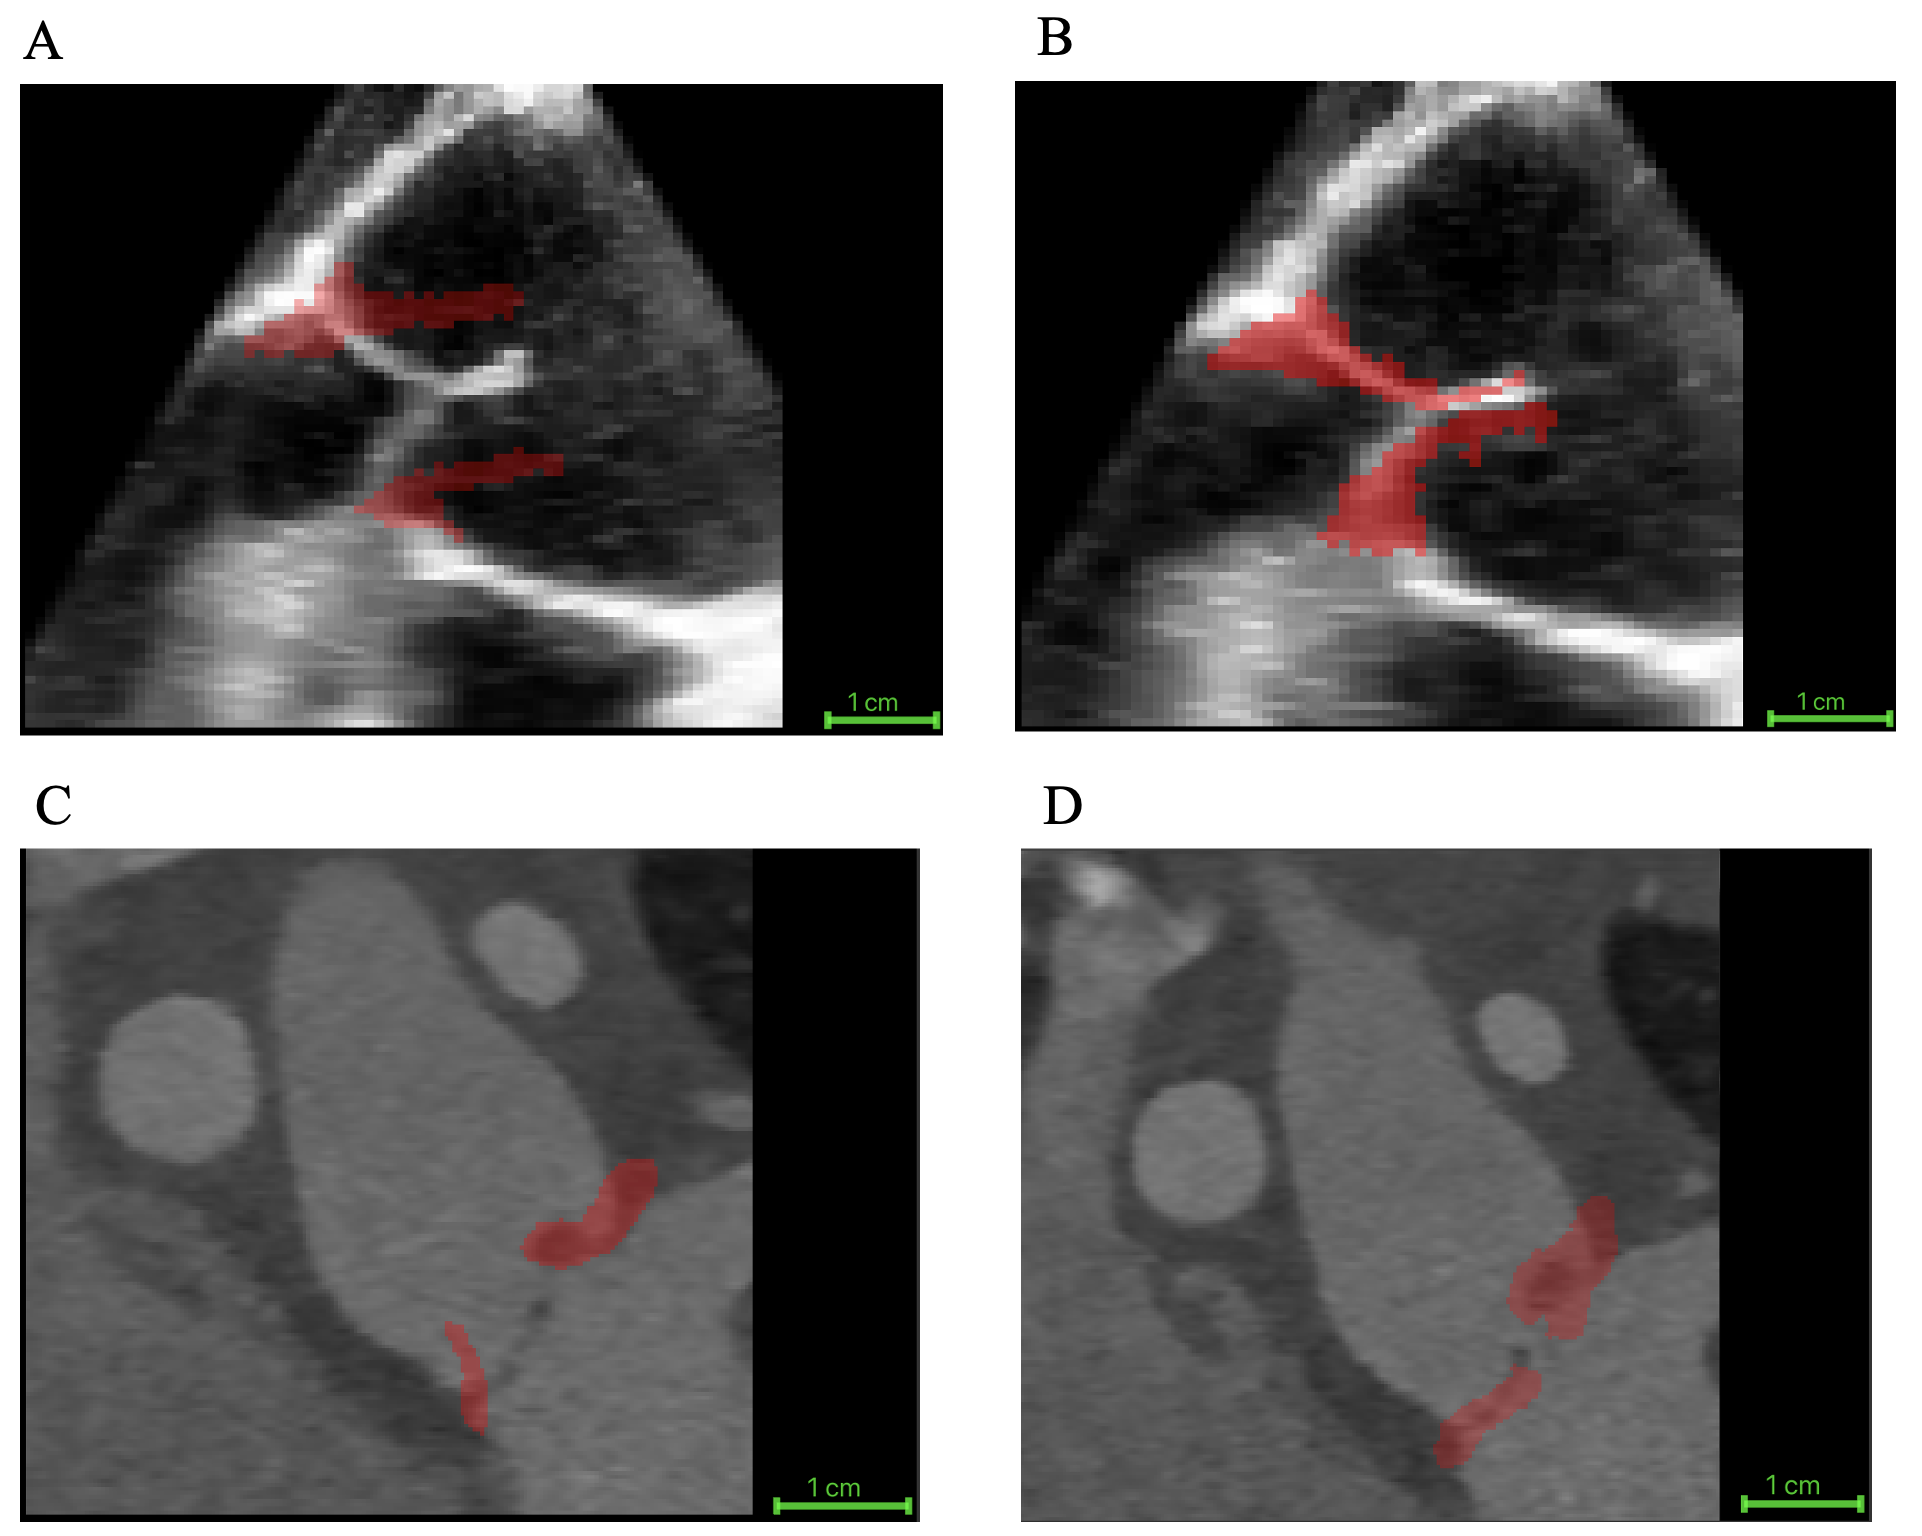

The proposed biomechanically informed registration improved segmentation-tracking accuracy by an average of 40%, reflecting the reduction in the mean distance between the tracked closed-state segmentation and the manual ground truth across all 20 cases when compared with direct registration. Specifically, this mean distance decreased from 3.70 ± 2.30 mm with direct registration (no FEM) to 2.23 ± 1.27 mm using our approach. Figure 3 illustrates an example of the reconstructed patient-specific aortic valve closure (shown in red) overlaid on mid-diastole grayscale images. Panels A and B show a TEE case, and panels C and D show a CT case. For each modality, the left panel displays the result from direct registration, and the right panel shows the result from the FEM-augmented registration method. Furthermore, to assess the biomechanical behavior of different valve morphologies, we evaluated leaflet strain in adult trileaflet, adult bicuspid, and pediatric cases and compared the resulting strain ranges. The resulting strain maps exhibited physiologically consistent patterns.

Refer to caption

Figure 3: Example of image-based registration results for one TEE case and one CT case. The reconstructed aortic valve leaflets at mid-diastole are shown in red. (A) TEE with direct registration, (B) TEE with FEM-augmented registration, (C) CT with direct registration, and (D) CT with FEM-augmented registration.